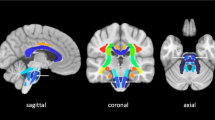

DTI changes were more pronounced in cWM than in cGM. The FA in contralateral cWM steadily declined (p = 0.003), without evidence of recovery during the follow-up period. FA in cGM followed a similar trend; however, the slope was not statistically significant. The decline in cWM FA contralateral to the supratentorial lesion was associated with an increase in radial diffusivity (p = 0.04), with no systematic change in the axial diffusivity (Fig. 3).

Asymmetry of fractional anisotropy (FA) versus axial diffusivity (AD) and radial diffusivity (RD) in cerebellar the cerebellar white matter. The FA asymmetry values are the same as shown in Fig. 2, and there was a significant negative correlation between FA and RD. FA was not associated with AD